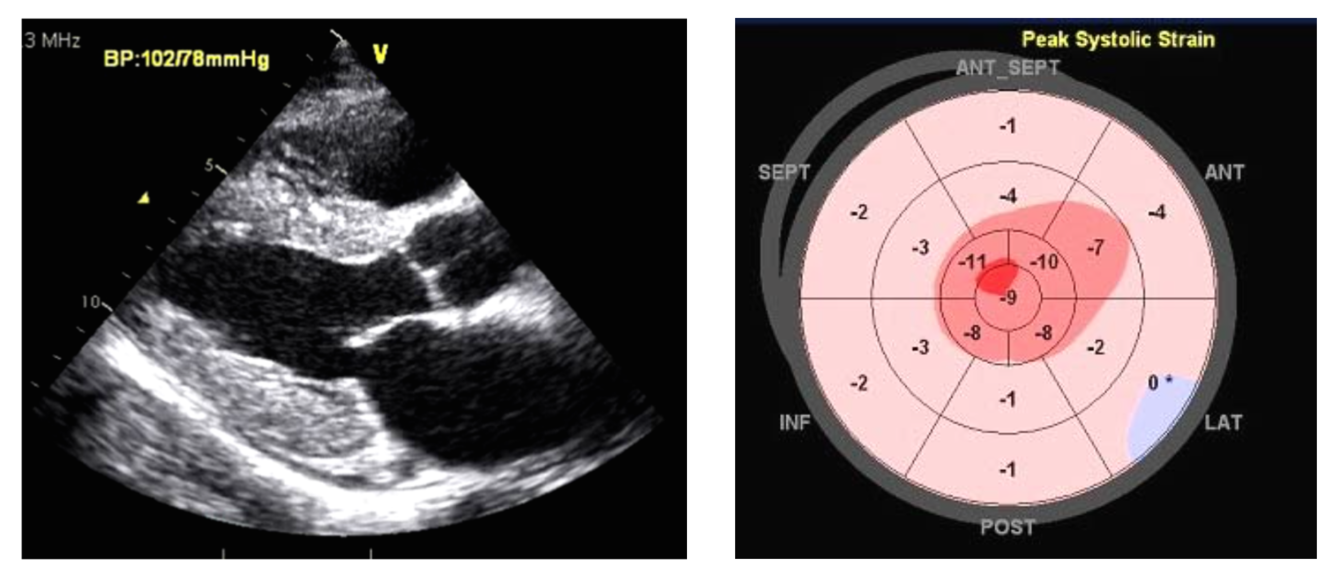

Diagnosis?

Amyloidosis